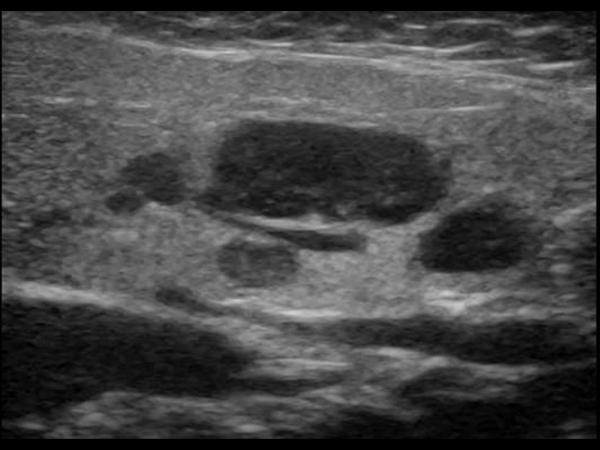

- سنگ غده بزاقی (سیالیتیاز): در این بیماری با رسوب کلسیمی جلوی جریان بزاقی را می گیرد که باعث درد و تورم در غده ی بزاقی می شود. سنگ غده ی بزاقی بیشتر در غده ی تحت فکی و پاروتید دیده می شود.